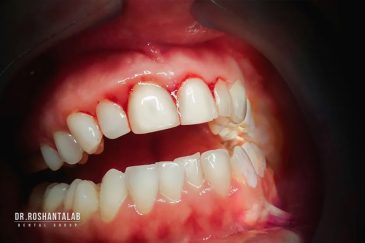

دندانپزشکی زیبایی

طراحی لبخند هالیوودی با متدهای لمینت سرامیکی دندان و کامپوزیت ونیر در کنار اصلاح فرم، خدمات بلیچینگ و روکش دندان، زیبایی چهره شما را تکمیل میکند.ترمیم دندان